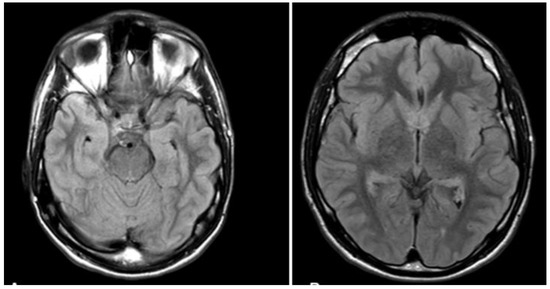

The study involved L, a 19-year-old, right-handed man without any history of psychiatric or neurological disorders. L is in the first year of a BA Law degree. In a dissociative fugue episode on 9 December 2020, L suddenly found himself at the railway station and had no idea about what he was doing there or even about his own name, age, and address. After being questioned by the police at the station, L was taken by the health service to the neurology department of the Nantes Hospital. During the neurological exam, L was conscious and had no neurological/psychiatric symptoms. The medical exam showed normal heart condition and blood pressure. L was also examined with magnetic resonance imaging (MRI) performed with a 1.5-Tesla scanner with Diffusion Tensor Imaging, T1-weighted without and with contrast agent, and 3D T2-SPACE fluid-attenuated inversion recovery (FLAIR) sequences. As illustrated in Figure 1, MRI showed no cerebral abnormality.

Figure 1. MRI scans of L.